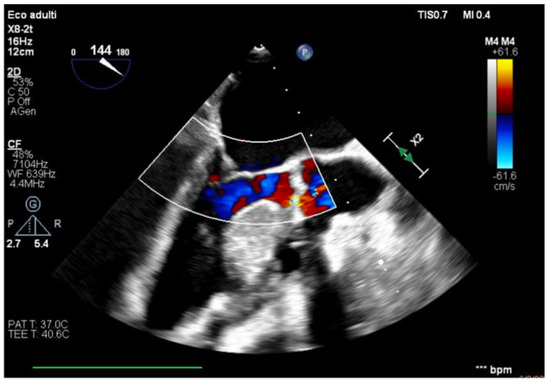

The transesophageal echocardiography showed LVOT-VTI 10 cm; apical, septal, and anterior wall akinesia; preserved function of the medium-basal segments of the inferior and lateral walls (Figure 3, Figure 4 and Figure 5); and RV-FAC 39% with an unloaded right ventricle (Figure 6).

Figure 3. TG mid-papillary level, the day after surgery (T0).